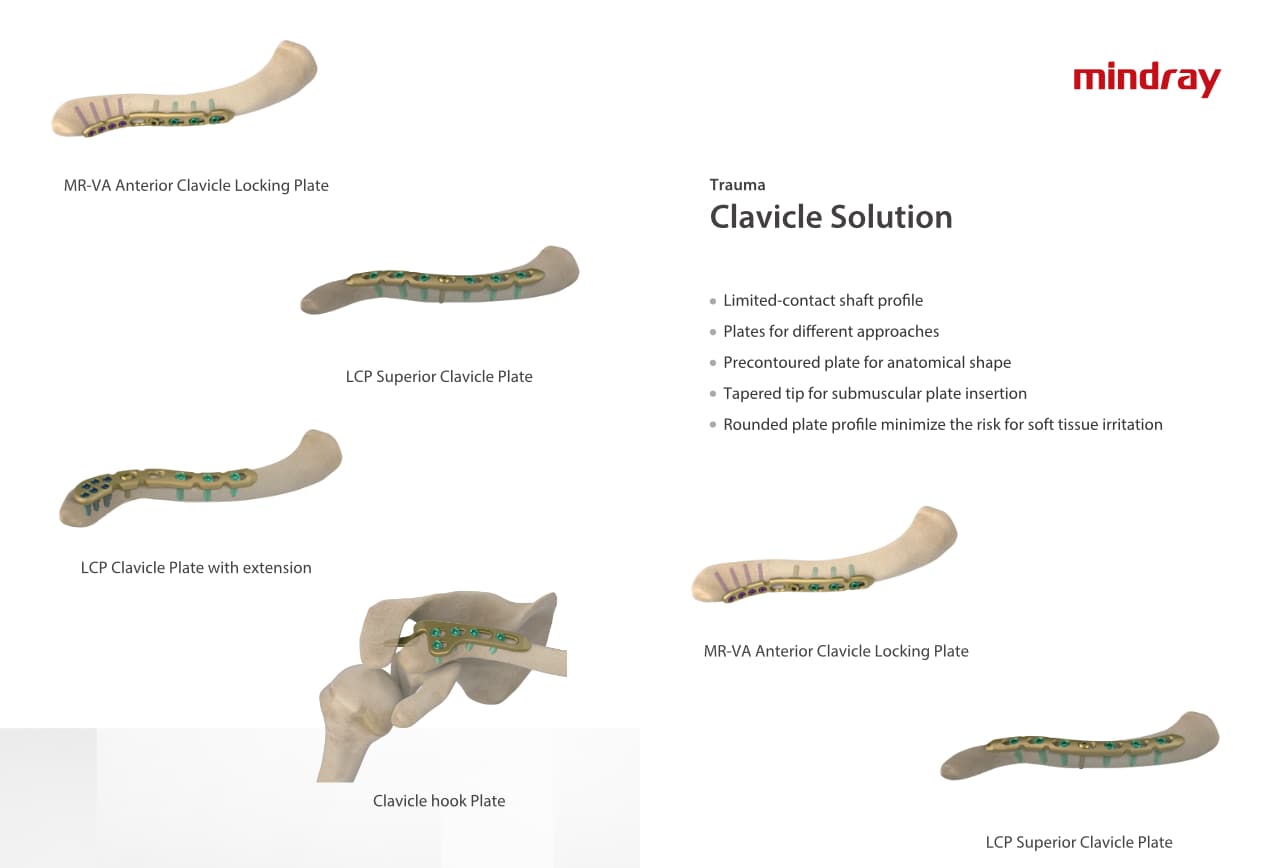

РһСҖСӮРҫРҝРөРҙРёСҮРөСҒРәРҫРө РҝРҫРҙСҖазРҙРөР»РөРҪРёРө РәРҫРјРҝР°РҪРёРё Mindray, СҖР°СҒРҝРҫР»РҫР¶РөРҪРҪРҫРө РІ РЈС…Р°РҪРө, СҸРІР»СҸРөСӮСҒСҸ РҫРҙРҪРёРј РёР· РІРөРҙСғСүРёС… РҝСҖРҫРёР·РІРҫРҙРёСӮРөР»РөР№ РҫСҖСӮРҫРҝРөРҙРёСҮРөСҒРәРҫР№ РҝСҖРҫРҙСғРәСҶРёРё РёР· РҡРёСӮР°СҸ. РһРҪРҫ Р·Р°РҪРёРјР°РөСӮСҒСҸ РёСҒСҒР»РөРҙРҫРІР°РҪРёСҸРјРё Рё СҖазСҖР°РұРҫСӮРәРҫР№, РҝСҖРҫРёР·РІРҫРҙСҒСӮРІРҫРј Рё РјР°СҖРәРөСӮРёРҪРіРҫРј СӮСҖавмаСӮРҫР»РҫРіРёСҮРөСҒРәРёС… Рё СҒРҝРёРҪалСҢРҪСӢС… РёР·РҙРөлий, РҝСҖРҫРҙСғРәСҶРёРё РҙР»СҸ Р°СҖСӮСҖРҫРҝлаСҒСӮРёРәРё Рё РҙСҖСғРіРёС… С…РёСҖСғСҖРіРёСҮРөСҒРәРёС… РёР·РҙРөлий. РЎ РјРҫРјРөРҪСӮР° СҒРІРҫРөРіРҫ РҫСҒРҪРҫРІР°РҪРёСҸ РІ 1999 РіРҫРҙСғ РјСӢ СғСҒРҝРөСҲРҪРҫ РҝСҖРҫСҲли СҒРөСҖСӮифиРәР°СҶРёСҺ ISO 9001, ISO 13485 Рё CE, РІСӢРҙР°РҪРҪСғСҺ T?V Рё СҚРәСҒРҝРҫСҖСӮРёСҖСғРөРј РҝСҖРҫРҙСғРәСҶРёСҺ РІ РұРҫР»РөРө СҮРөРј 50 СҒСӮСҖР°РҪ РҝРҫ РІСҒРөРјСғ РјРёСҖСғ.